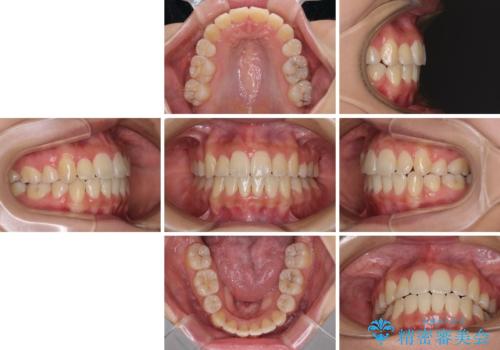

- 八重歯を気にして来院された患者様です。

上下ともに前突感と叢生が認められ、上顎の正中が著しく右側にずれていたため、上下左右第一小臼歯4本を抜歯し、ワイヤー矯正にて治療を行うこととしました。

移動量が多かったため、治療期間は通常より半年~1年ほど長くかかりましたが、上下の正中をほぼ同じ位置にまで移動させることができました。